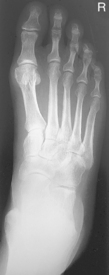

• Supine or seated with foot centered lengthwise to portion of IR being exposed

• Oblique foot 30°–40° medially, support with 45° radiolucent angle block and sandbags to prevent slippage

• Note 1: A higher arch requires nearer 45° oblique and a low arch “flat foot” nearer 30°.

• Note 2: A 30° lateral oblique projection will demonstrate the space between 1st and 2nd metatarsals and between 1st and 2nd cuneiforms.